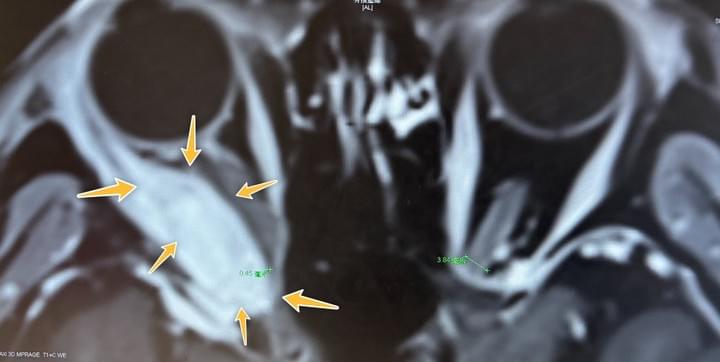

從一個奇特的眼內腫瘤病例

談到三種不同思維的外科醫師

2026-02-22

外科醫師和馬一樣(我們是醫界牛馬)也分爲上中下三駟。下駟級的醫師腦中只有一個技術念頭,他尋找手術適應症有時只是緊抓一個單一理由。他不太關心邏輯因果的反覆確認,只是在尋找一個合法開刀的理由。中駟級的醫師就會關心影像與臨床症狀的因果關係。他會多方確認病患的主訴與神經學檢查,並嘗試在影像或電生理檢查找到手術的支持證據。上駟級的醫師更多的是看到病患全貌,包含引起疾病的共病與用藥病史、家族史、生活習慣,甚至是工作與運動的細節。他會詳細爬梳每一個線索,建立所謂的疾病發生模型。並針對這個疾病模型,提出各種疾病的可能與介入診斷的選擇,並與病患家屬共同決定臨床決策。